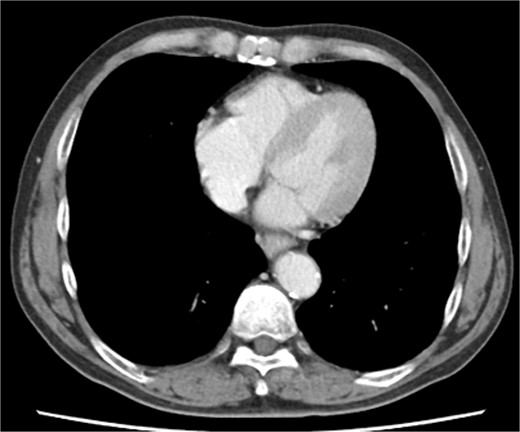

Immediately prior to surgery, he suffered cardiac arrest requiring cardiopulmonary resuscitation but recovered quickly, and a median sternotomy was performed expeditiously. Fortunately, no injury to the retrosternal gastric tube occurred. The gastric tube was pushed into the right thorax to expose the pericardial surface. A pericardial hematoma was observed, and pericardiotomy relieved the tamponade. Removal of the hematoma revealed a 5 mm aneurysm in the peripheral right ventricular branch with pulsatile bleeding (Fig. 4). Hemostasis was achieved using horizontal mattress suturing between the central and peripheral areas of the aneurysm without bypass grafting to the right ventricular branch artery by cardiac surgeon. In addition, TacoSeal® (CSL Behring, Pennsylvania, USA) and Volheal® (KM Biologics, Kumamoto City, Japan) were applied (Fig. 5). The operative time was 133 min, with a blood loss of 1160 ml. Oral intake was initiated on POD 5, and the patient was discharged on POD 22 with an unremarkable postoperative course.

A 5 mm aneurysm in the peripheral right ventricular branch with pulsatile bleeding is observed.